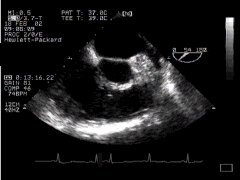

1. Two chamber view (LA, LV, MV) - 'ME 2 Chamber'

2. thumbnail ME SAX Longitudinal mid oesophageal 2 chamber view CLICK FOR VIDEO: mid oesophageal 2 chamber view  (longitudinal)

The left ventricular cavity and mitral valve are well seen. "Fine tuning" by careful probe movement can be used to demonstrate the papillary muscles and details of the mitral valve leaflets. (Inferior papillary muscle on your left, anterior on the right).